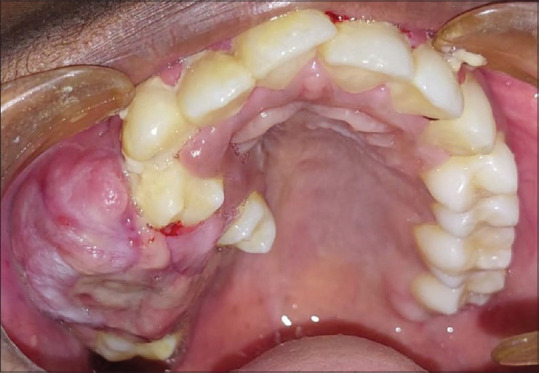

Patient concerns: A 14-year-old male patient reported with a chief complaint of swelling in the right upper back tooth region for four months.

Diagnosis: Incisional biopsy of the lesion shows numerous dilated and thin-walled blood vessels and focal areas of chronic inflammatory cell infiltrate beneath the epithelium suggestive of angiofibroma.

Treatment: Surgical excision of the lesion along with curettage was done under general anaesthesia. On histopathologic examination, the lesion revealed loose connective tissue stroma with mesenchymal cells and multinucleated giant cells suggestive of CGCG.